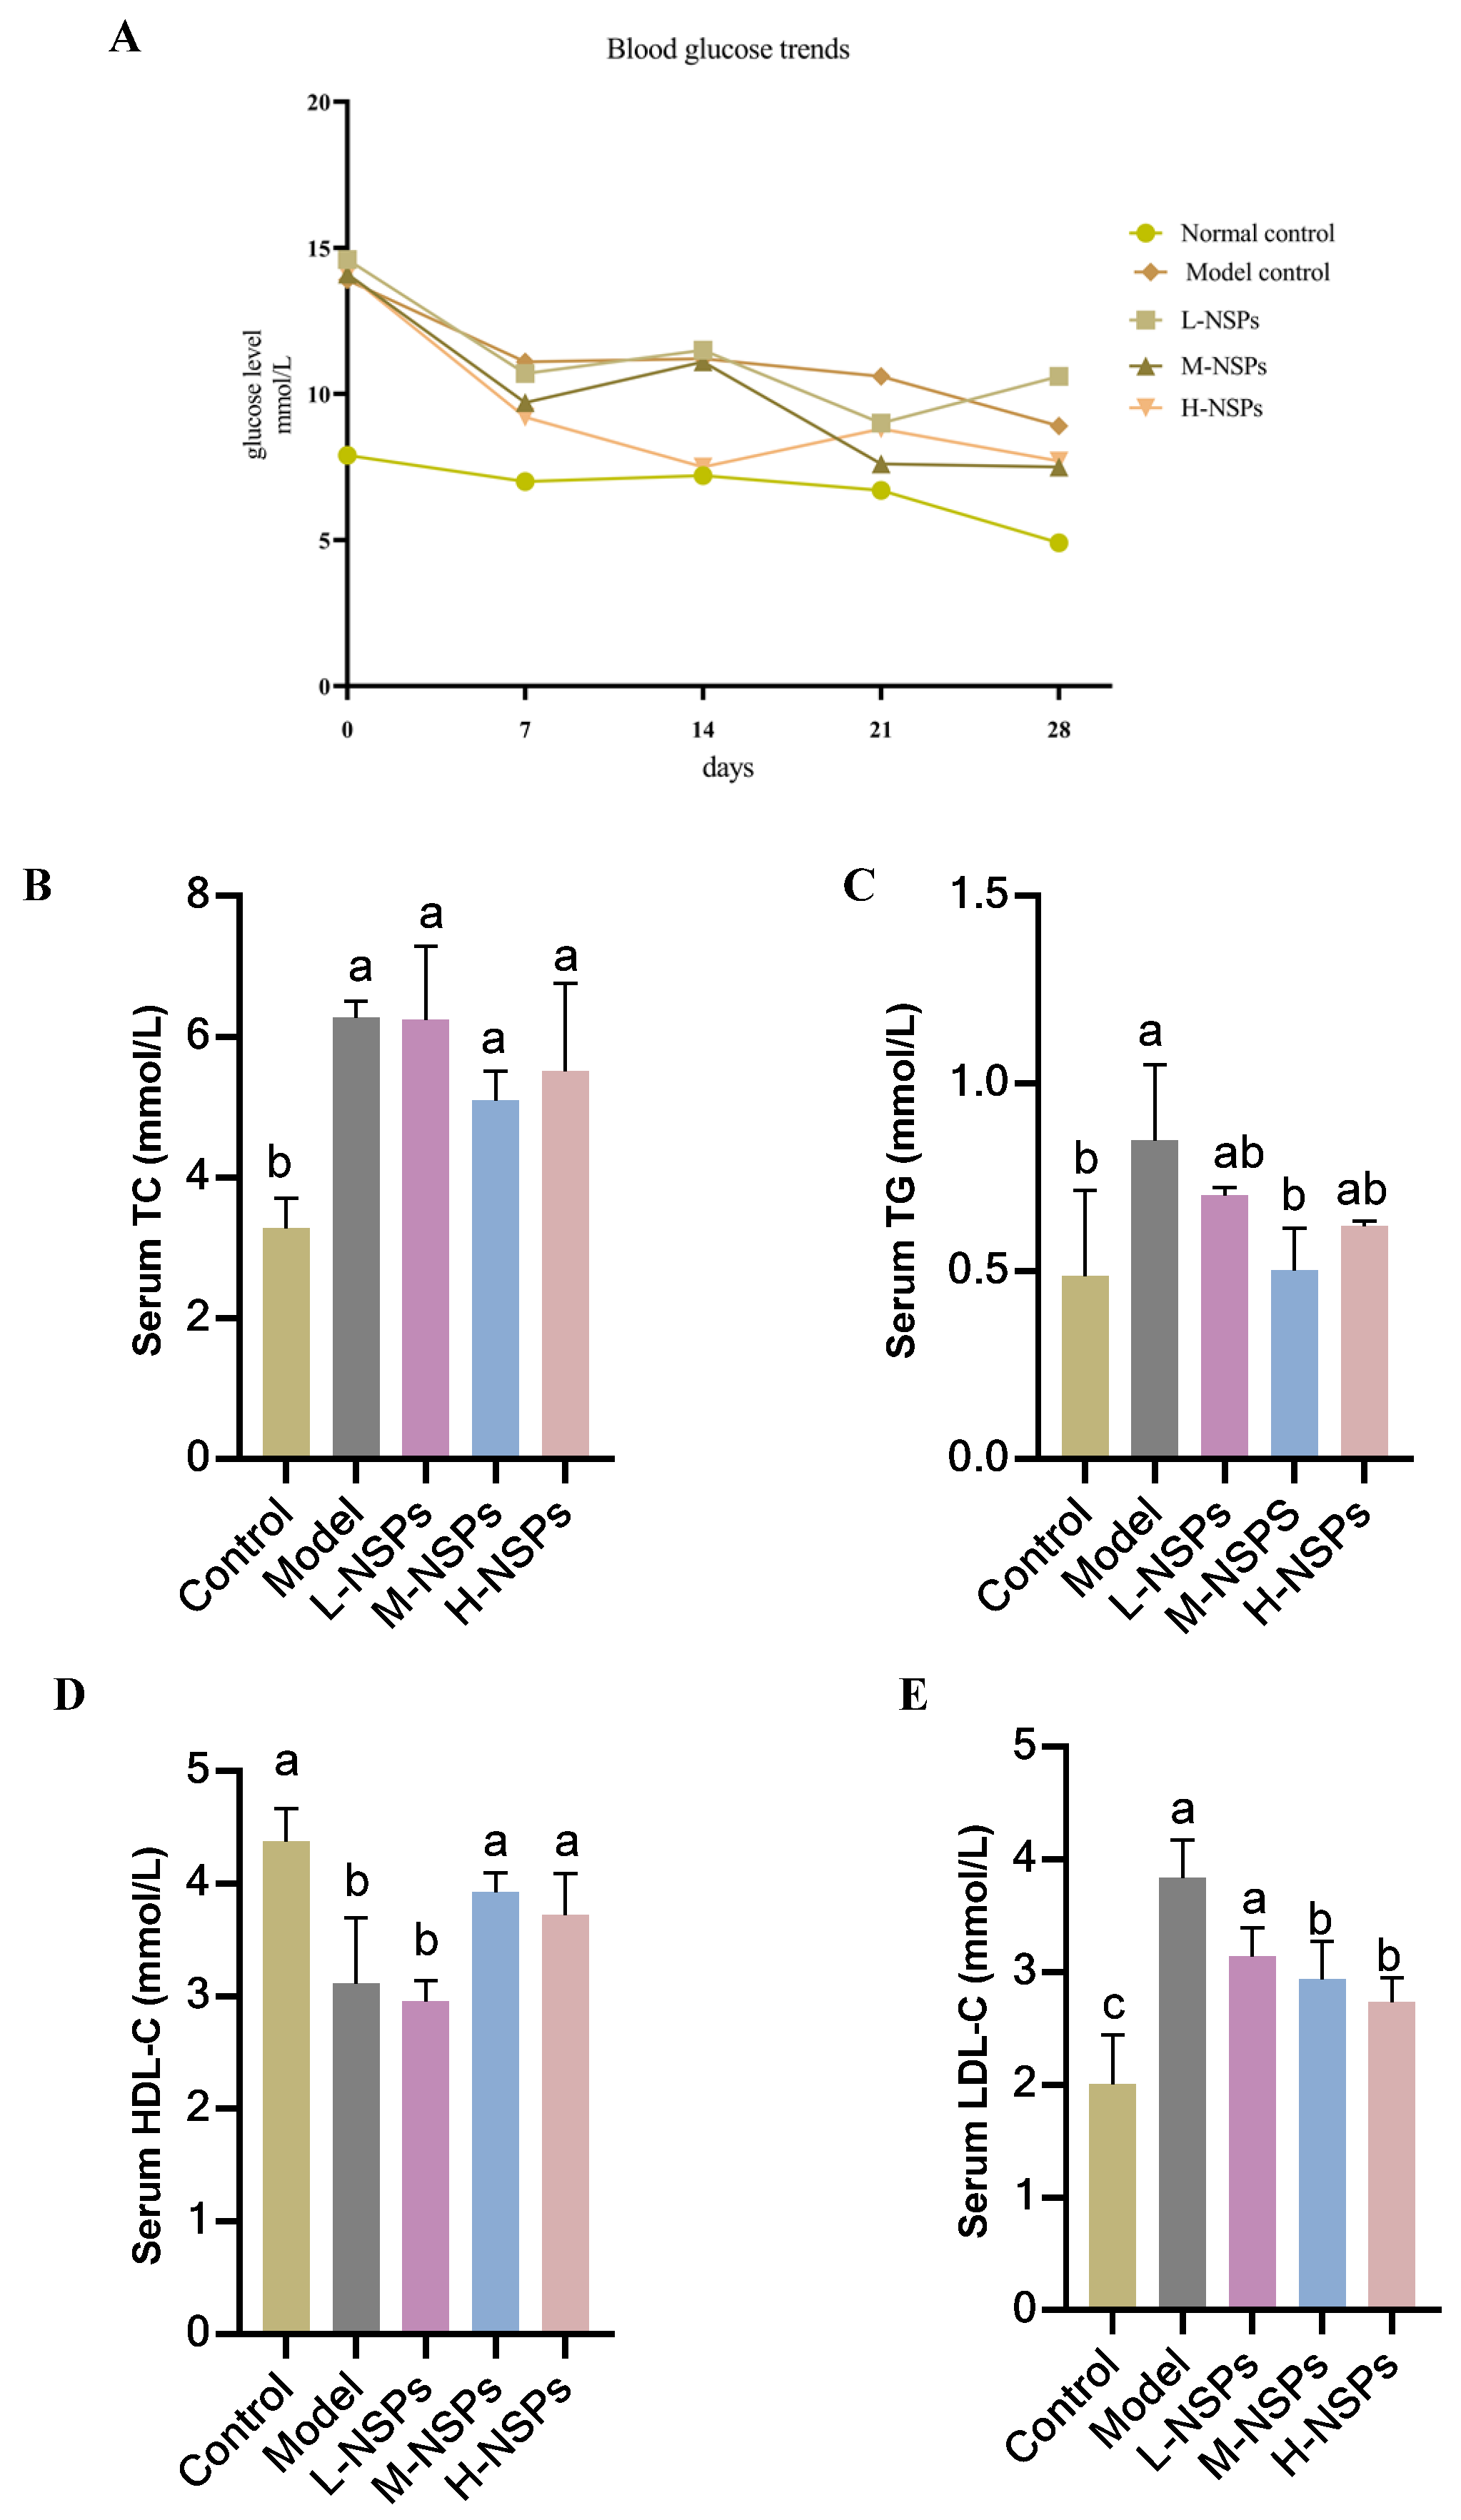

3.6. The Effect of NSPs on Mice Fasting Blood Glucose

3.7. The Effect of NSPs on Serum Lipid Profile